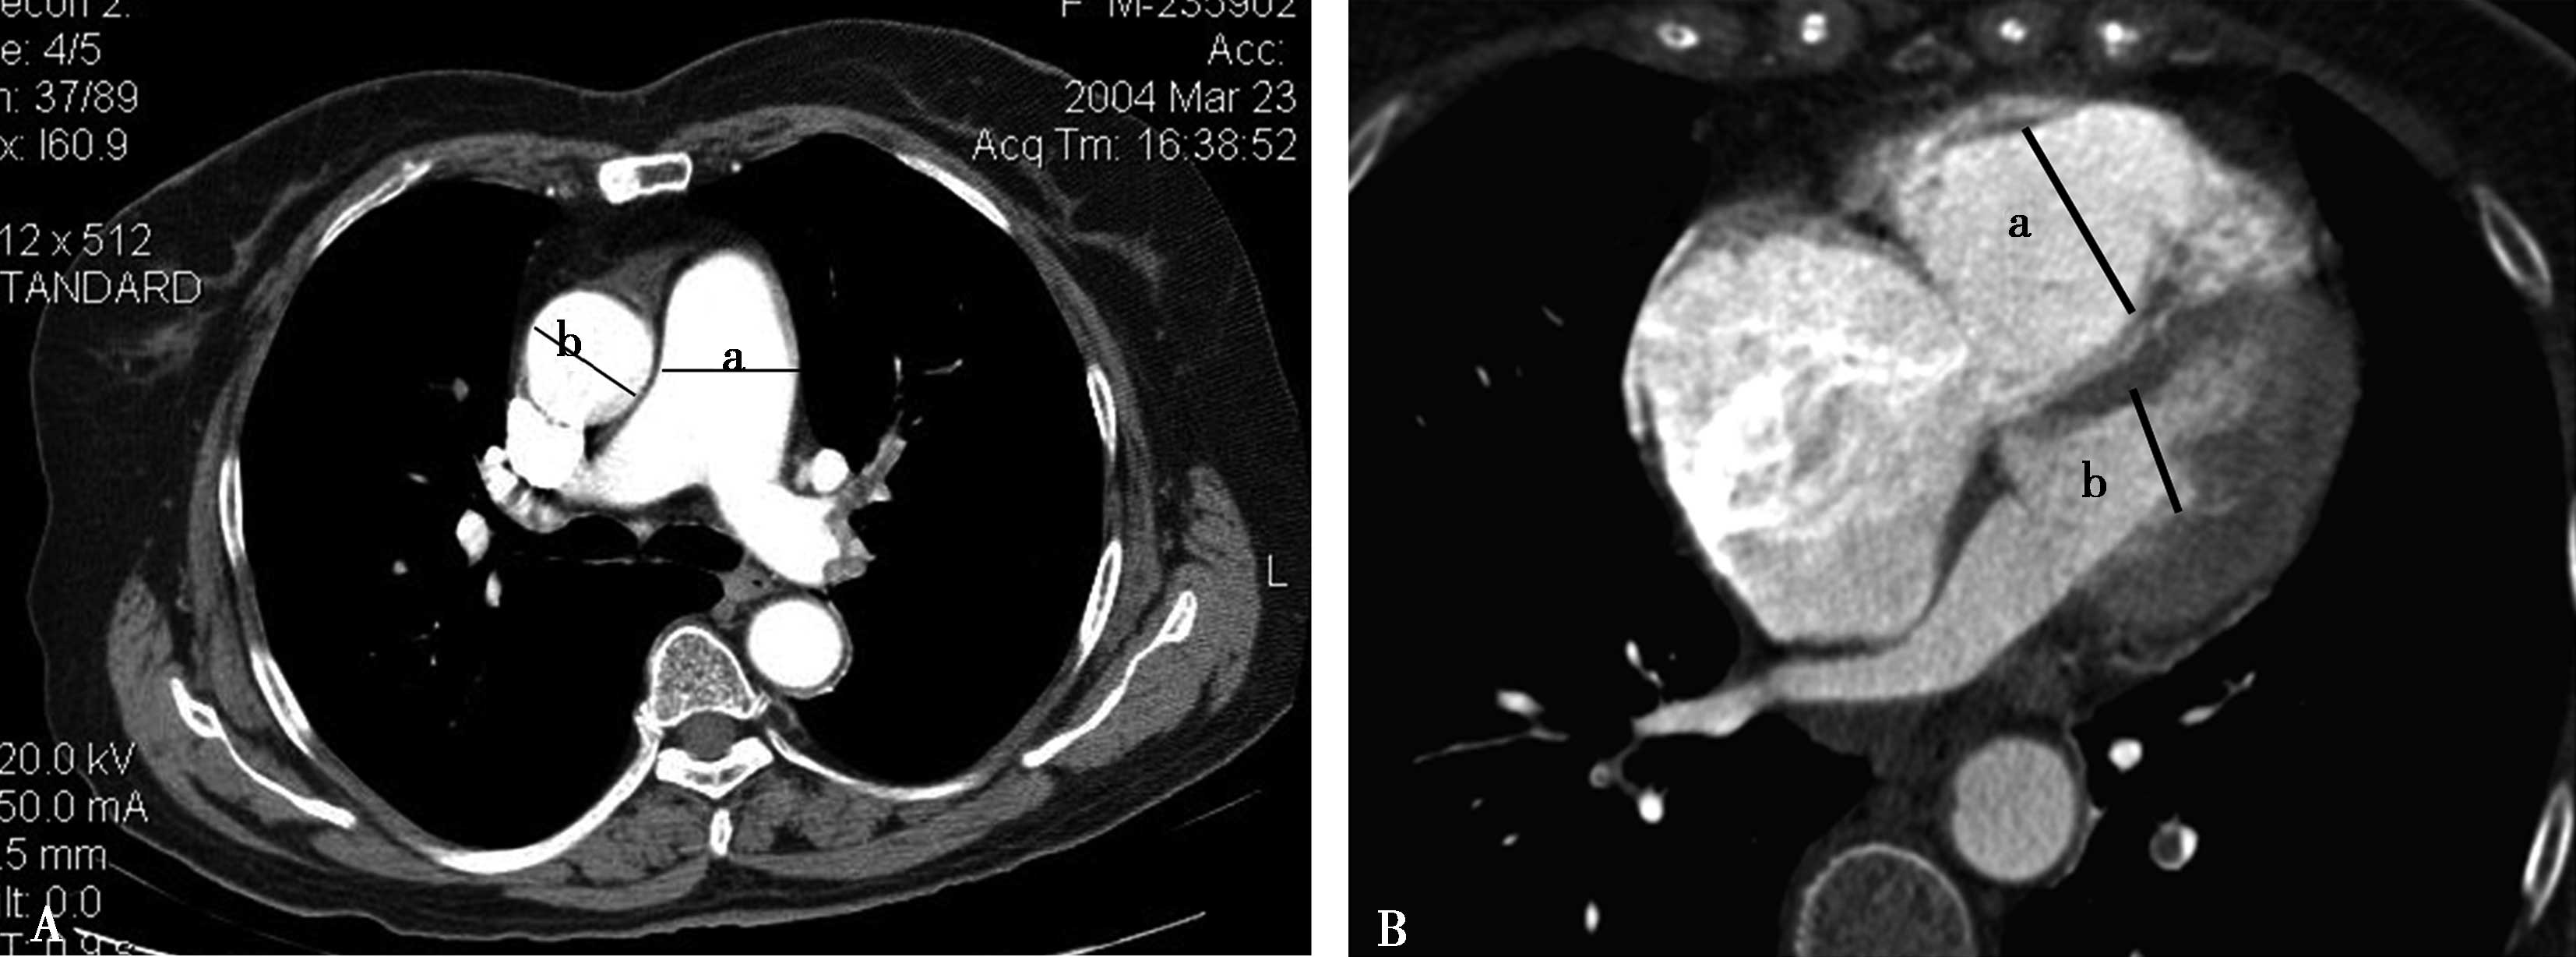

(三)多排螺旋CT右心功能评价

1.右心室增大

横断像心室最大层面测量左右心室最大横径(图8-3-10),正常心脏右心室横径:左心室横径<1,(a∶b<1),室间隔居中(红色↑)。右心室增大,右心室横径:左心室横径>1,(a∶b>1),室间隔凸向左心室(红色↑)。

图8-3-10 横断图像

A.正常心脏,a∶b<1; B.右心室增大,a∶b>1